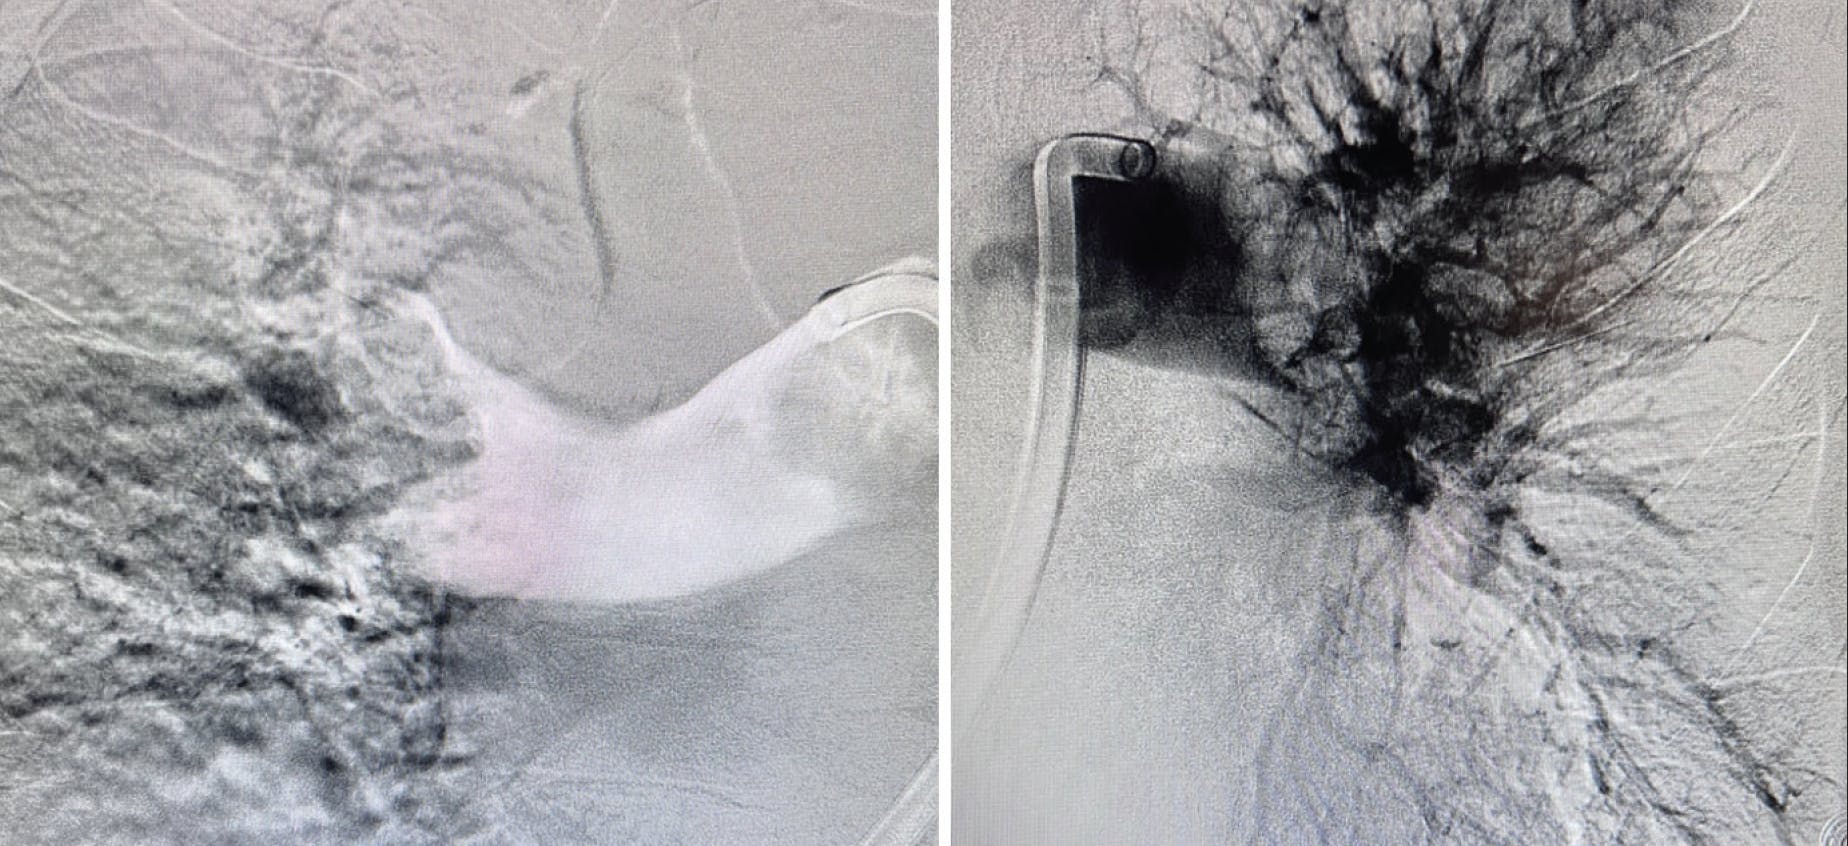

Pulmonary angiography demonstrated extensive thrombus in the left main PA and moderate distal thrombi in the right PA (Figure 3). The access site was preclosed with one Perclose ProGlide device (Abbott), and the sheath was upsized to a 16-F Gore DrySeal Flex introducer sheath (Gore & Associates) after serial dilation. A long J wire was advanced into the right PA, followed by introduction of the CAT16 aspiration catheter. After wire removal, CAVT was initiated, and multiple passes in the left PA extracted a significant amount of thrombus (Figure 4). Postthrombectomy angiography revealed marked reduction in clot burden (Figure 5). The total case time was 45 minutes, with a 3-minute device time using Lightning Flash 2.0. Final hemodynamics showed a PAP of 41/19 mm Hg (mean, 28 mm Hg). The 16-F sheath was removed, and hemostasis was achieved with one Perclose ProGlide.

Figure 3. Initial angiogram revealing extensive thrombus in the main PA.

Figure 5. Postthrombectomy angiogram revealing significant reduction in clot burden.